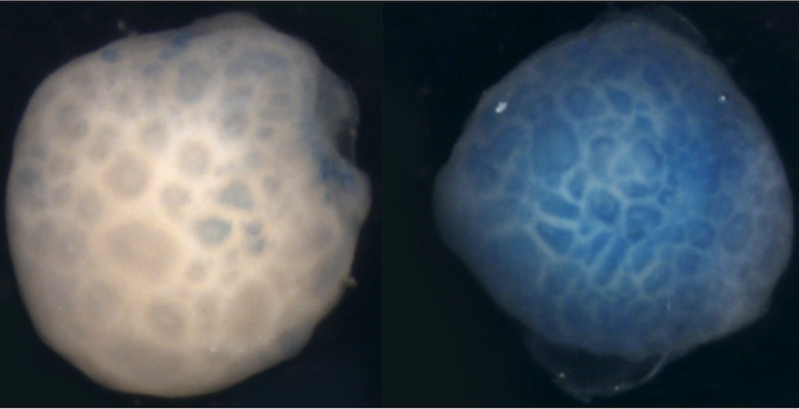

Ensuite, ils ont observé des résultats similaires dans des cellules neuroépithéliales humaines grâce à l’utilisation d’organoïdes, des structures utilisées pour simuler le développement du cerveau humain.